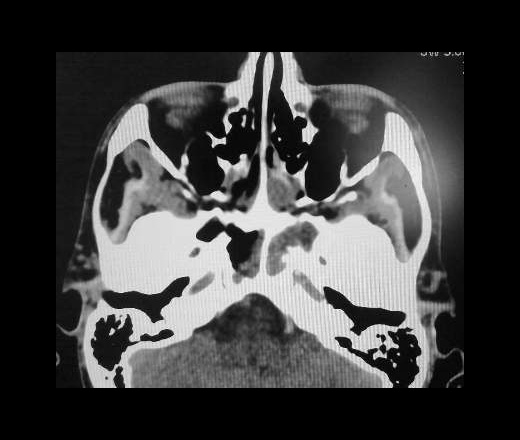

КТ-снимки хронического этмоидита: подробная визуализация